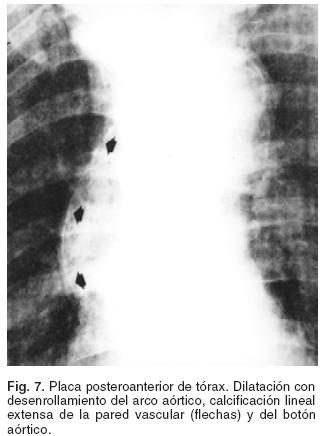

La aortitis luética debe sospecharse en todo sujeto con antecedentes de chancro primario o lesiones mucocutáneas secundarias y sin tratamiento previo, en quien se demuestre calcificación lineal de la pared aórtica en la placa posteroanterior (PA) del tórax (Fig. 7), imagen registrada sólo en el 25% de los sifilíticos en etapa tardía.3 Cuando la prueba serológica de absorción de anticuerpos fluorescentes (FTA–ABS) o de inmovilización del Treponema (TI) son positivas se confirma el diagnóstico etiológico, hecho de gran beneficio para el enfermo porque la indicación de un tratamiento oportuno suele prevenir las complicaciones más graves de la enfermedad.4,24–26